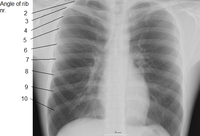

الضلع Rib واحد من العظام الأربعة والعشرين التي تحيط بالصدر في جسم الإنسان. وهناك اثنا عشر ضلعًا في كل جانب من جانبي الجسم، يَتصِل كل واحد منها بالعمود الفقري بوساطة وصلات تسمى الفقرات. وفي مقدمة الجسم، ترتبط الأضلاع السبعة العلوية في كل جانب مباشرة بالعظمة الصدرية بوساطة مادة صلبة مطاطية تسمى الغضاريف، وتُسمى هذه الأضلاع، الأضلاع الحقيقية. أما الأضلاع الخمسة التي تحتها وتُسمى الأضلاع الإضافية، فليست مُتصلة بعظمة الصدر بشكل مباشر، بل إن كل واحد من الأضلاع الثلاثة العلوية الإضافية، مُتصل بالضلع الذي يعلو الغضروف. أما الضلعان اللذان يقعان في الأسفل، فإنهما مُتَصلان بعظمة الظهر. ويُعرفان باسم الضلعين السائبين. وتحتوي الفراغات الموجودة بين الأضلاع، والتي تُسمَّى فراغات بين الأضلاع، على الشرايين والأوردة والعضلات والأعصاب.

تقسيم الاضلاع في الإنسان

- أول سبعة أزواج من الاضلاع تسمى "الأضلاع الحقيقية". وهي متصلة بسشكل مباشر بعظم القص.

- ازواج الاضلاع الثلاثة التالية تسمى بالأضلاع الكاذبة " وهي تتصل بعظم القص بواسطة غضروف.

- اخر زوجين من الاضلاع تسمى " الأضلاع السابحة " وهي متصلة بالعمود الفقري ولا تتصل بعظم القص.

بين الأضلاع يوجد عضلات، أوعية دموية وأعصاب.